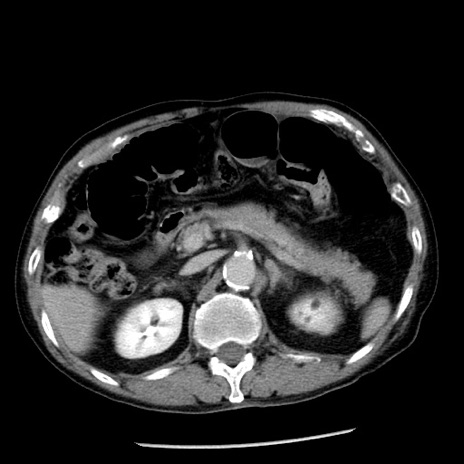

症例26(横断像)

【症例】80歳代男性

【主訴】嘔吐

【現病歴】昨晩2回嘔吐あり、今朝になっても嘔吐あり。来院。

【既往歴】胃潰瘍

【身体所見】意識清明、BT 37.6℃、BP 166/95mmHg、HR 100bpm、SpO2 97%、腹部:平坦・軟、腸蠕動音聴取良好、圧痛なし。

【データ】WBC 21900、CRP 1.46